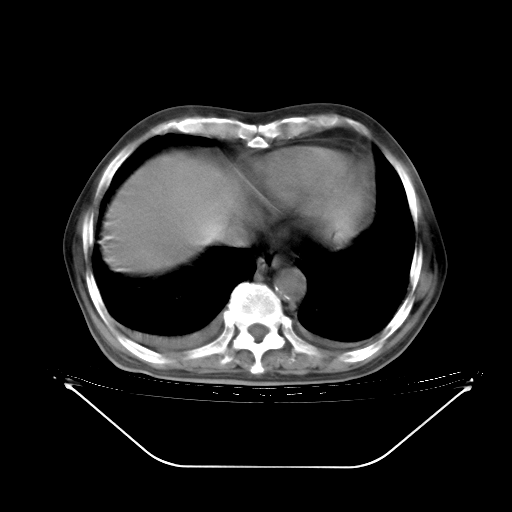

胸腹部CT,诊断意见:左上肺叶钙化灶、左侧胸膜局限性增厚并钙化、胆囊炎。描述部分肺组织呈磨玻璃样改变。

今天复查肺部CT,发现双肺广泛磨玻璃样改变。所以我把3月19日和5月9日相隔50天的肺部CT上传。请大家会诊。

2009年3月19日肺部CT片。

5月9日肺部CT(在4月27日齐鲁医院肺部CT描述部分肺组织磨玻璃样改变,12天后肺组织广泛磨玻璃样改变)